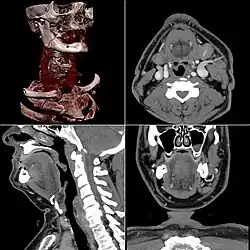

Топографическая анатомия (хирургическая анатомия) — научно-прикладная дисциплина, раздел анатомии, изучающий послойное строение анатомических областей, взаиморасположение (синтопию) органов, их проекцию на кожу (голотопию), отношение к скелету (скелетотопию), кровоснабжение, иннервацию и лимфоотток в условиях нормы и патологии, с учётом возрастных, половых и конституциональных особенностей организма.

Топографическая анатомия изучает строение человеческого организма по условно выделяемым известным частям тела (голова, шея, туловище и конечности), каждая из которых дифференцируется на относительно небольшие анатомические области.